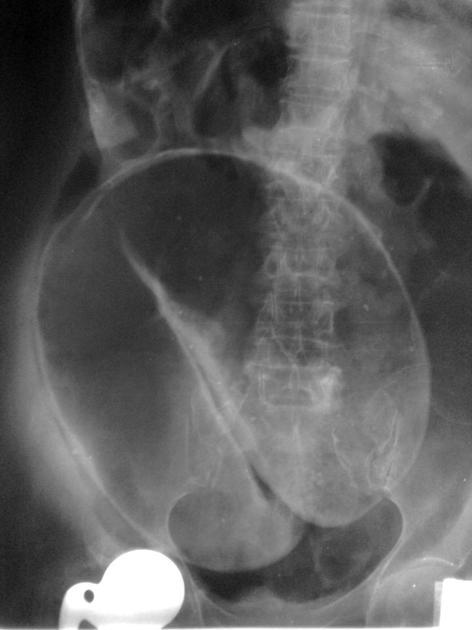

Petit papi avec un gros ventre, arrêt des matières et des gaz depuis 24h. Il a bien mal comme il faut. Vous lui faites un ASP alors que ce n’est plus dans les reco HAS: qu’est ce que c’est?

A

Volvulus du sigmoïde